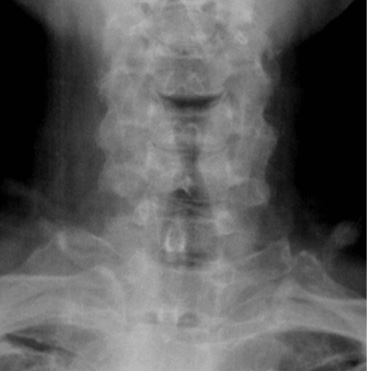

Pre-op dynamic radiographs demonstrate partial loss of disc height at C5-6 and C6-7 without instability or scoliosis.